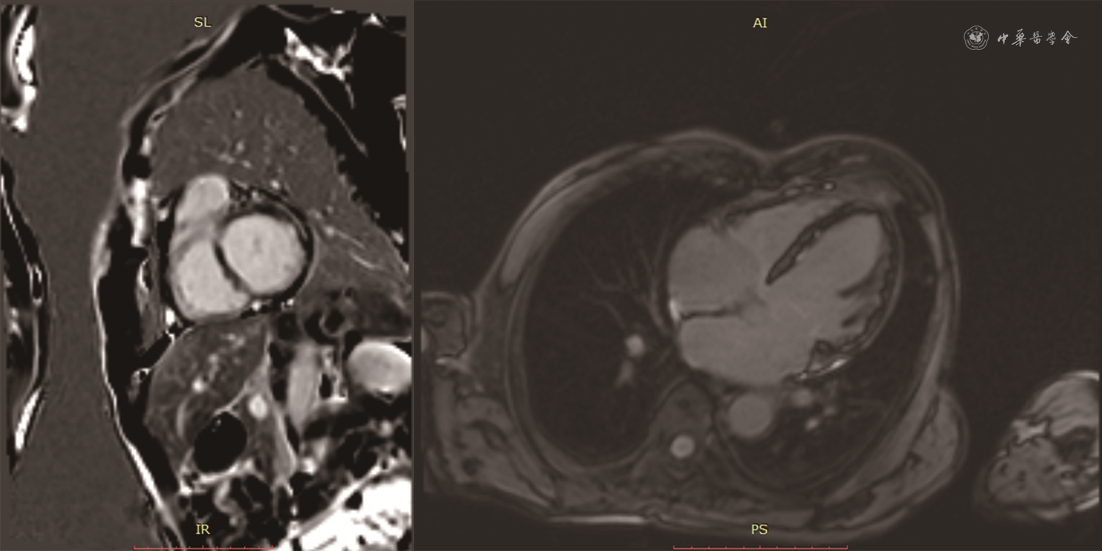

患者男,68岁,主因“胸痛、后背痛1 d”于2019年12月25日入院。患者有支气管哮喘病史,长期口服孟鲁司特。否认系统病史,否认食物、药物过敏史。无疫水、疫区接触史,无寄生虫接触史。入院体格检查:体温36.2 ℃,脉搏71次/min,呼吸25次/min,血压85/45 mmHg(1 mmHg=0.133 kPa)。神清语利,查体合作。浅表淋巴结未触及肿大。双肺呼吸音粗,可闻及肺底湿性啰音。心脏律齐,各瓣膜未闻及明显病理性杂音。腹软,无压痛及反跳痛。双下肢无水肿。血常规:白细胞计数22.39×109/L,嗜酸性粒细胞绝对值16.71×109/L[参考值(0.05~0.50)×109/L]。血浆D-二聚体1 027 μg/L(参考值<500 μg/L),肌钙蛋白T 2.950 μg/L,N末端B型利钠肽原9 949 ng/L(参考值0~1 800 ng/L),C反应蛋白1.32 mg/dl,免疫球蛋白E 421 IU/ml。心电图:窦律,完全性右束支传导阻滞。超声心动图:左心室舒张末期内径(LVEDD)58 mm,左心室收缩末期内径(LVESD)42 mm,左心房前后径43 mm,右心房左右径44 mm,左心室壁节段性运动异常,二尖瓣、三尖瓣中重度反流,下腔静脉内径增宽,左心室射血分数(LVEF)为43%,肺动脉收缩压70 mmHg(图1)。冠状动脉CT血管造影(CTA):冠状动脉呈右优势型,左、右冠状动脉未见有意义狭窄。给予补液、多巴胺、甲基泼尼龙静脉滴注以及口服甲泼尼龙等对症治疗,血压可维持在90/60 mmHg左右。2020年1月5日复查超声心动图:下腔静脉增宽,左心室壁运动普遍减弱,左心室收缩、舒张功能下降,二尖瓣轻度反流,主动脉瓣、三尖瓣轻度反流,心包积液(少量),肺动脉收缩压45 mmHg。骨髓(胸骨、髂骨)细胞学检查:粒细胞系统、红细胞系统、巨细胞系统三系增生,骨髓嗜酸性粒细胞增多。骨髓病理:骨髓增生低下,粒细胞与红细胞比例略增高,偏成熟为主,巨核细胞数量正常,形态未见特殊,可见散在嗜酸性粒细胞,稍多。基因检查报告:未检测到FIP1L1/PDGFRα融合基因,未检测到PDGFRβ、PGFR1、TEL-ABL1基因重排,未检测到JAK2基因分离重排。患者症状好转,生命体征平稳出院。出院诊断:特发性嗜酸性粒细胞增多症,Löeffler心内膜炎,心律失常(完全性右束支传导阻滞),纽约心脏协会(NYHA)心功能Ⅱ级、肺动脉高压、支气管哮喘。出院后口服甲泼尼龙片半年。出院后5个月随访,患者血常规正常,2020年5月28日复查超声心动图示LVEDD 57 mm、LVESD 42 mm、左心房前后径35 mm、右心房左右径41 mm、左心室壁节段性运动异常、二尖瓣和三尖瓣轻中度反流、LVEF为54%、肺动脉收缩压30 mmHg(图2)。2020年6月12日完善心脏磁共振检查,可见心脏饱满,左心室游离壁心肌变薄,以乳头肌至心尖水平外侧壁为著,右心室心肌形态未见明确异常,左、右心室收缩及舒张功能未见明确异常。钆对比剂延迟强化(LGE)见左心室心内膜区多发斑点状,二尖瓣、三尖瓣未见明显反流信号,提示左心室心肌弥漫性损伤,符合Löeffler心内膜炎表现(图3)。考虑心脏重构有加重趋势,除继续给予口服甲泼尼龙片外,加用沙库巴曲缬沙坦(ARNI)抑制心脏重构。出院后9个月(2020年9月21日)再次复查超声心动图(图4):LVEDD 50 mm,LVESD 35 mm,左心房前后径34 mm,右心房左右径37 mm,左心室壁节段性运动异常,二尖瓣、三尖瓣轻度反流,LVEF 56%,肺动脉收缩压30 mmHg。